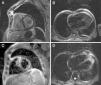

In order to better understand the hemodynamics, right heart catheterization was performed and revealed poor RV function with high filling pressures, normal pulmonary artery pressures, mildly depressed cardiac index, normal pulmonary capillary wedge pressure and normal pulmonary vascular resistance (Table 1). Importantly, a deep y descent with a rapid upstroke was noted (‘square root’ sign), suggesting severe diastolic filling impairment (Figure 1). To further clarify the myocardial disorder in the absence of pulmonary hypertension, CMR was performed, which showed diffuse infiltration of the myocardium (Figure 2). This was later confirmed by endomyocardial biopsy which was notable for diffuse myocardial fibrosis (Figure 3).

CMR is currently the noninvasive method of choice to assess diffuse myocarditis, providing information on the stage, degree, and extent of reversible and irreversible myocardial injury.13 T1- and T2-weighted CMR are novel techniques for quantitative tissue characterization, which may overcome the limitations of current CMR criteria for assessing diffuse myocardial damage.13,14 Recent studies indicate that native myocardial T1, myocardial T2, and extracellular volume (ECV) imaging could improve the diagnostic performance of CMR.14,15